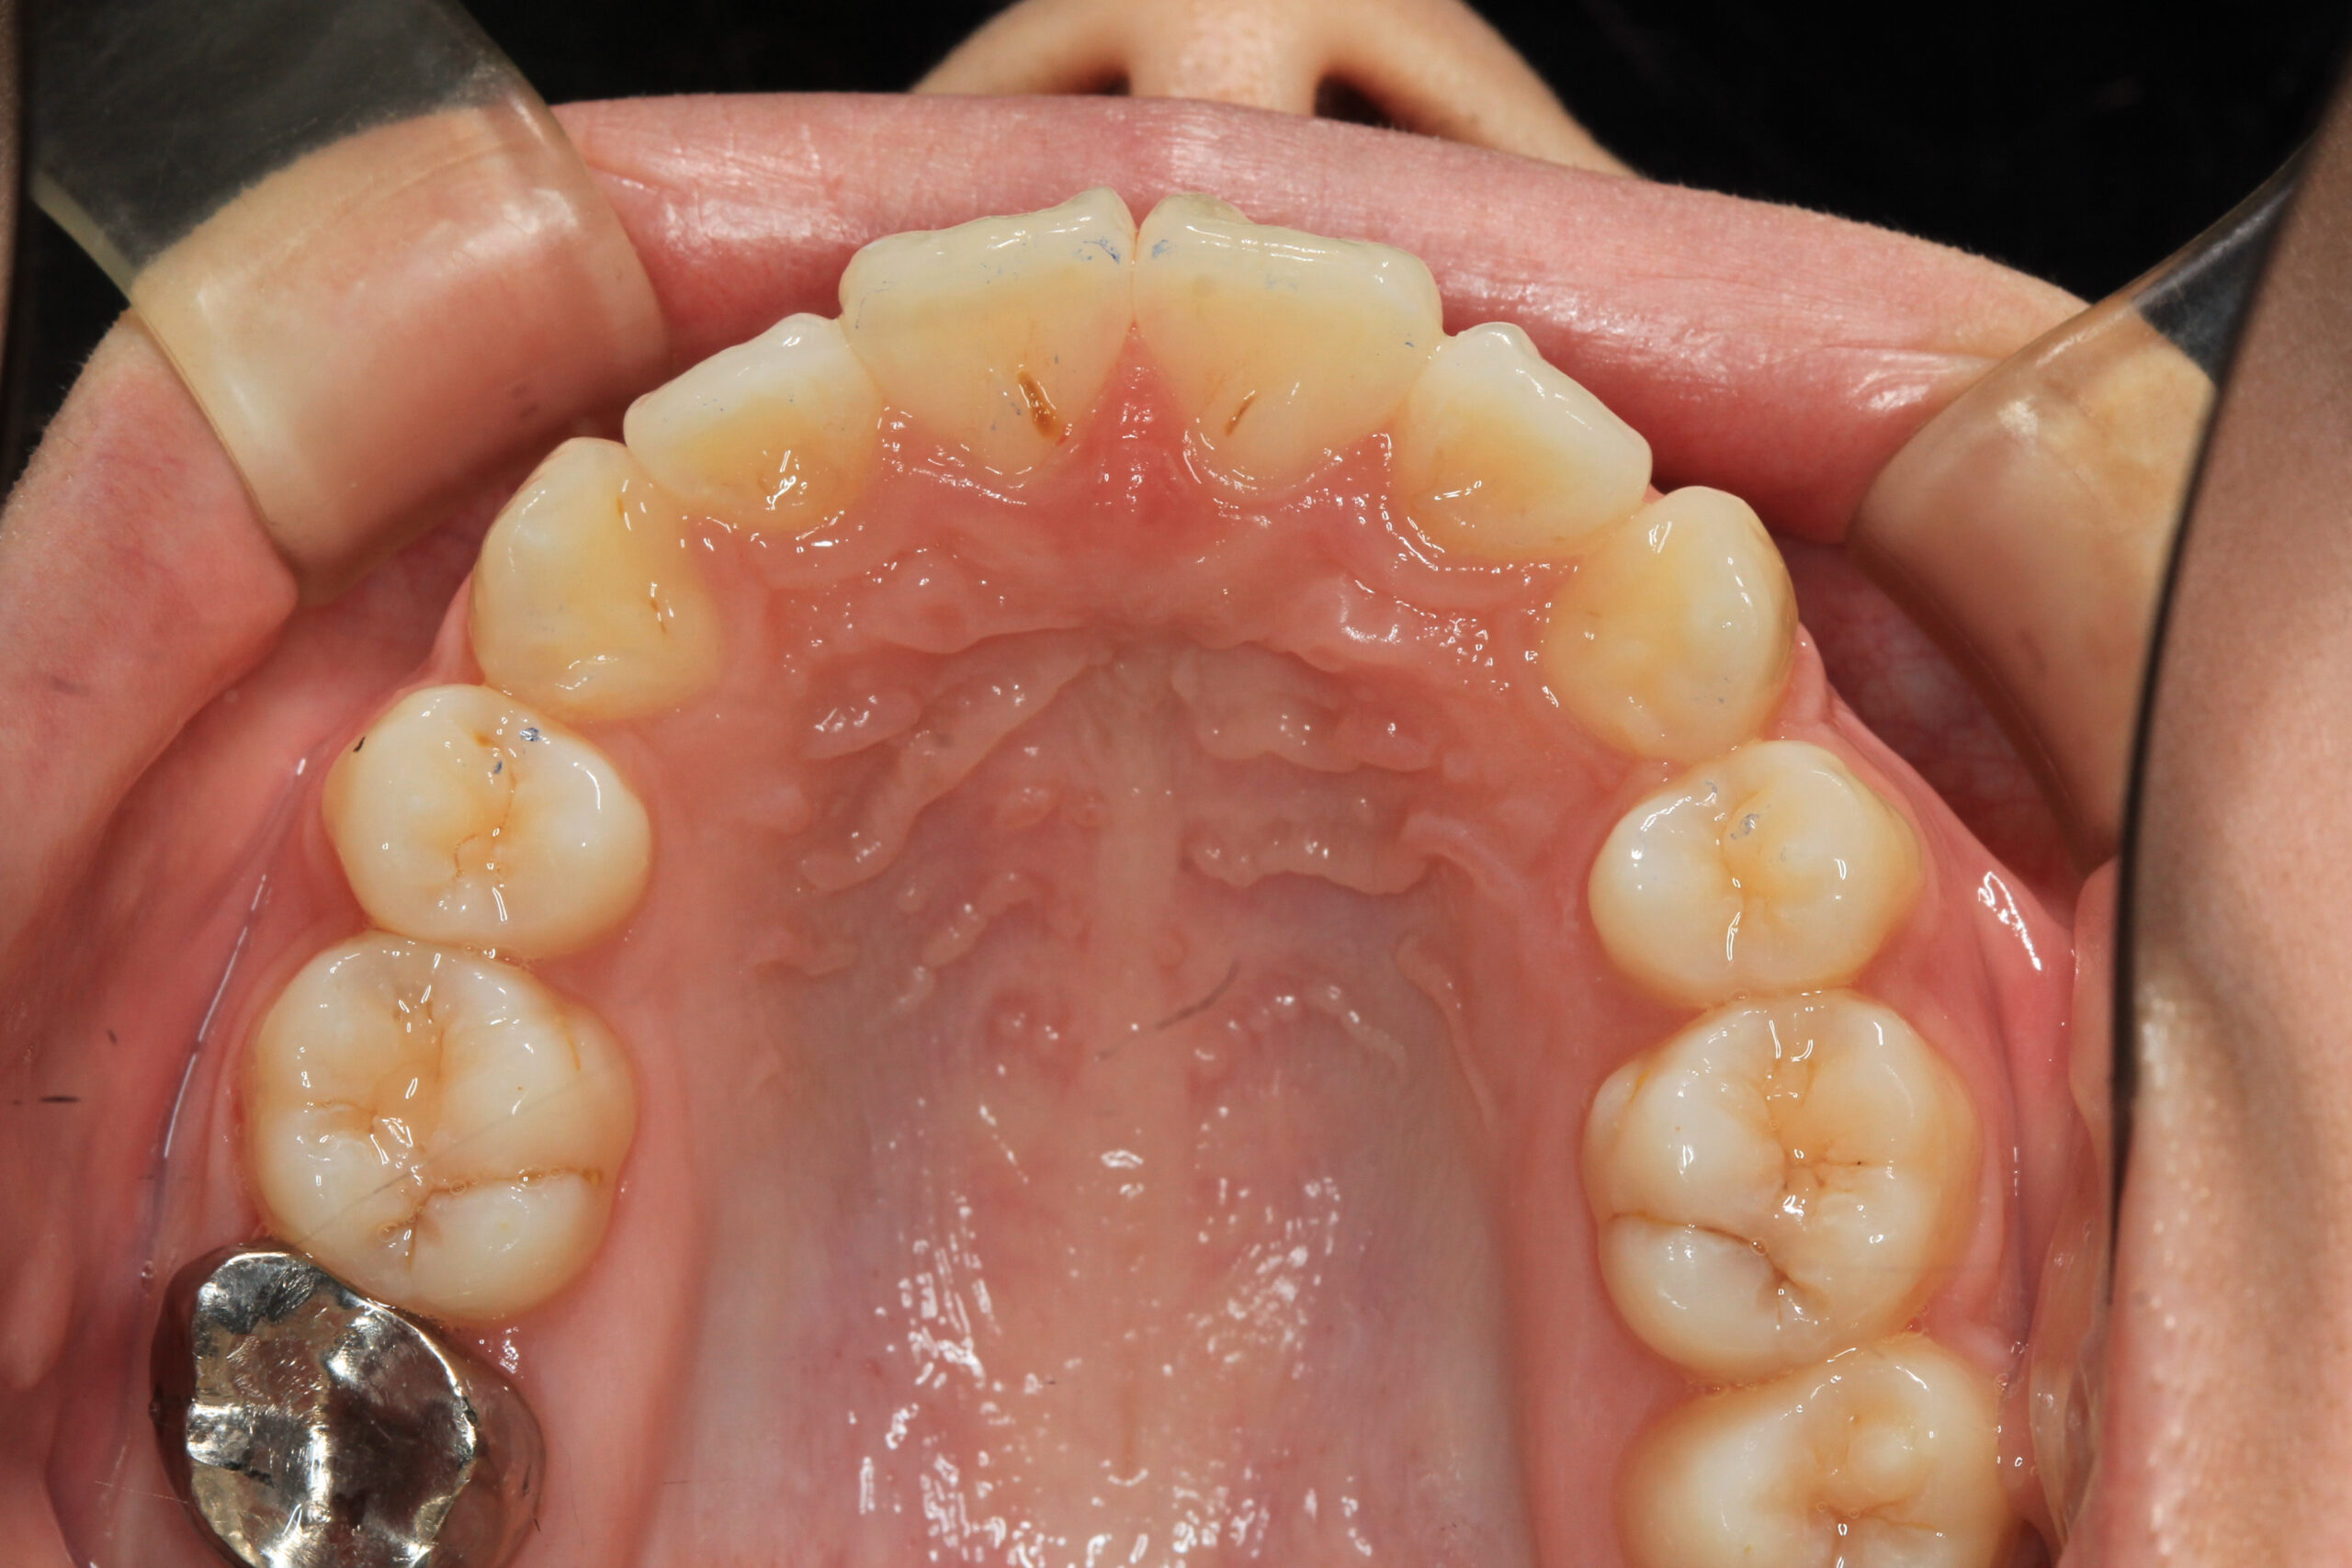

左右の小臼歯を抜歯し綺麗に改善しました。

上の写真と比べてください、オーバージェット感も抜群に綺麗になりました。

通常抜歯矯正となりますと大体3年前後かかると言うのが普通なのですが今回は文明の利器である加速矯正装置をインビザラインと併用し僅か1年3か月でこの様に改善出来ました。

ここまでのガタガタをインビザラインで抜歯矯正できればもうワイヤー矯正なんて必要ないんじゃないかと思うくらい綺麗な出来です。